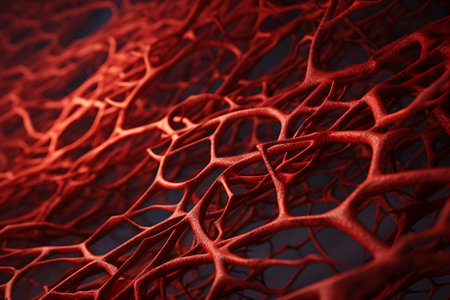

Layout of blood vessels in the human body. 3D model.

A microscopic view of blood vessels, conveying the intricate network that sustains life

Blood vessels

A microscopic view of blood vessels, conveying the intricate network that sustains life